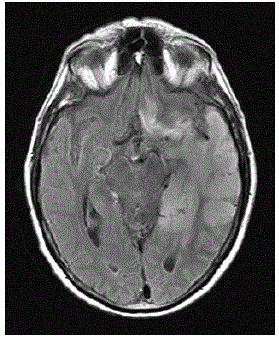

ATENÇÃO: O caso seguinte se refere às questões 38 e 39:

Mulher, 52 anos de idade, veio trazida ao Pronto-Socorro por queixa de cefaleia e uma crise tônico-clônica generalizada que ocorreu dois dias antes da admissão. Em seguida evoluiu com sonolência. Ao exame de admissão tem temperatura de 38ºC, PA 100x60 mmHg, FC: 112bpm e restante do exame clínico geral sem alterações. No exame neurológico, encontrava-se sonolenta, com abertura ocular aos estímulos verbais vigorosos, retirada inespecífica dos membros à dor, falando palavras desconexas, reflexos profundos globalmente vivos e reflexo cutâneo plantar em flexão bilateral. Também foram observadas algumas clonias em hemiface direita. Tomografia computadorizada de crânio mostrou uma hipoatenuação em lobo temporal esquerdo. Exames laboratoriais revelaram uma leucocitose de 13500 sem desvios à esquerda e um aumento da proteína C reativa. Foi então submetida a uma punção lombar para coleta de líquor cujo resultado foi de 41 células (66% de linfócitos, 32% de monócitos e 2% de neutrófilos), 48 hemácias, proteína de 59 mg/dL, glicose de 64 mg/dL e lactato de 25 mg/dL.